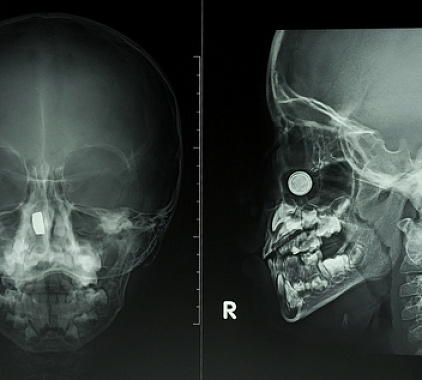

Чаще всего, протокол исследования включает в себя описание следующих тонкостей рентгена носоглотки в норме:

- Наличие переломов и деформаций носовой кости.

- Образования округлой формы, расположенные у стенок синуса вблизи носовых пазух, определяющиеся как кисты. Новообразования на рентгенограмме носоглотки визуализируются как тени с нечетким контуром.

- Описанию поддаются миндалины, так как при просвете носоглотки хорошо видно степень гипертрофии и общее состояние аденоидов.